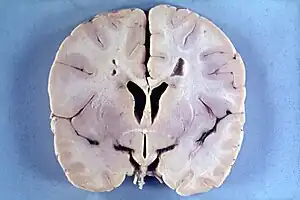

Many people with abnormally large heads or large skulls are healthy, but macrocephaly may be pathological. Pathologic macrocephaly may be due to megalencephaly (enlarged brain), hydrocephalus (abnormally increased cerebrospinal fluid), cranial hyperostosis (bone overgrowth), and other conditions. Pathologic macrocephaly is called "syndromic", when it is associated with any other noteworthy condition, and "nonsyndromic" otherwise. Pathologic macrocephaly may be caused by congenital anatomic abnormalities, genetic conditions, or by environmental events.[3]

Environmental events associated with macrocephaly include infection, neonatal intraventricular hemorrhage (bleeding within the infant brain), subdural hematoma (bleeding beneath the outer lining of the brain), subdural effusion (collection of fluid beneath the outer lining of the brain), and arachnoid cysts (cysts on the brain surface).[3]